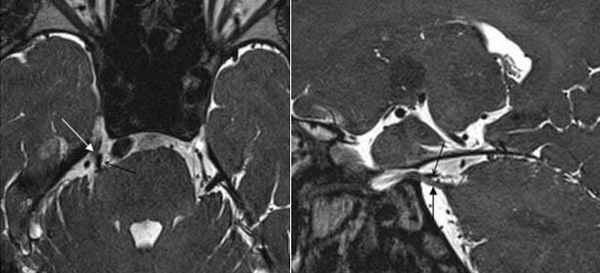

Аксиальный срез (А, Б), сагиттальная проекция (В). Определяется нейроваскулярный конфликт между артерией и тройничным нервом. Компрессия тройничного нерва прилежащей к нему артерией обозначена стрелкой.

Определяется близкое расположение артериального сосуда и лицевого нерва (указано стрелкой), что может являться причиной гемифациального спазма

Определяются признаки компрессии лицевого нерва около ствола головного мозга крупным артериальным сосудом – позвоночной артерией (указано стрелкой).

Визуализируется близкое расположение артериального сосуда и лицевого нерва (указано стрелкой), что может являться причиной гемифациального спазма